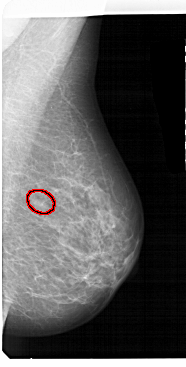

A_1563_1.LEFT_MLO

LEFT_MLO LINES 5491 PIXELS_PER_LINE 3181 BITS_PER_PIXEL 12 RESOLUTION 43.5 NON_OVERLAY

FILE: A_1563_1.RIGHT_MLO.OVERLAY

TOTAL_ABNORMALITIES 1

ABNORMALITY 1

LESION_TYPE MASS SHAPE OVAL MARGINS ILL_DEFINED

ASSESSMENT 4

SUBTLETY 4

PATHOLOGY BENIGN

TOTAL_OUTLINES 1

BOUNDARY